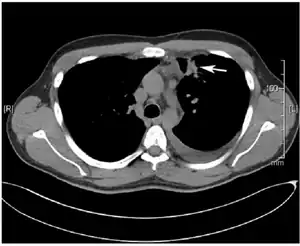

Several diagnostic signs indicate a lung fluke infection. These include a cough, fever, and weight loss.[2] Pleural effusion, a condition in which a surplus of fluid accumulates around the lungs, is another sign of an infection. P. kellicotti infection may sometimes be misdiagnosed as tuberculosis. However, a lung fluke infection is differentiated from tuberculosis by increased eosinophils in the blood and pleural fluid.